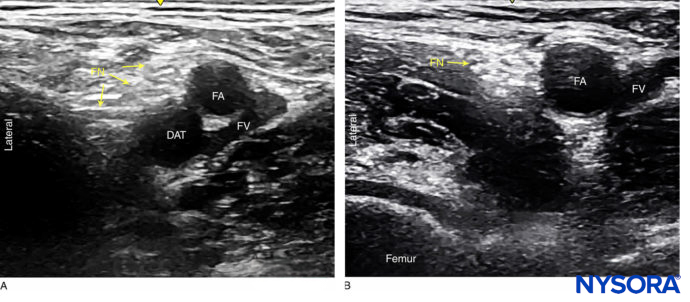

Orientation begins with the identification of the femoral artery at the level of the femoral crease. Commonly, the femoral artery and the deep artery of the thigh are both seen. In this case, the transducer should be moved proximally until only the femoral artery is seen (Figure 1a, b). The femoral nerve is lateral to the vessel and covered by the fascia iliaca; it is typically hyperechoic and roughly triangular or oval in shape (Figure 2a, b). The nerve is enveloped within two layers of the fascia iliaca. The femoral nerve typically is visualized at a depth of 2–4 cm.

FIGURE 1. Femoral nerve (FN) as seen distally (A) and at the femoral crease (B) Note that FN is better visualized at B, before the take off the deep artery of the thigh (DAT). Femoral vein (FV) is medial to the artery.